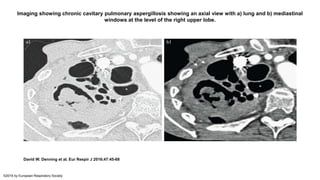

Imaging showing chronic cavitary pulmonary aspergillosis showing an axial view with a) lung and b) mediastinal

windows at the level of the right upper lobe.

David W. Denning et al. Eur Respir J 2016;47:45-68

©2016 by European Respiratory Society

• Radiographic imaging reveals one or more thick- or thin-walled cavities

that often have irregular walls and intracavitary material; aspergillomas

may develop within the cavities as the disease progresses. The upper

lobes are most commonly affected. As the disease progresses, new

cavities develop or existing cavities expand, and they may coalesce or

perforate into the pleural space.

• Infiltrates are common surrounding the cavities. The thickness of cavity

walls represents the inflammatory activity of the disease as well as

possible adjacent fibrosis. For lesions close to the pleura, pleural

thickening is very common. Concomitant findings include bronchiectasis,

nodules, ground glass changes, tree-in-bud changes, and organizing

pneumonia.

• #18 Imaging showing chronic cavitary pulmonary aspergillosis showing an axial view with a) lung and b) mediastinal windows at the level of the right upper lobe. Multiple cavities are visible with a fungus ball lying within the largest one. The wall of the cavities cannot be distinguished from the thickened pleura or the neighbouring alveolar consolidation. The extra pleural fat is hyperattenuated (white arrows). *: the dilated oesophagus should not be confused with a cavity.